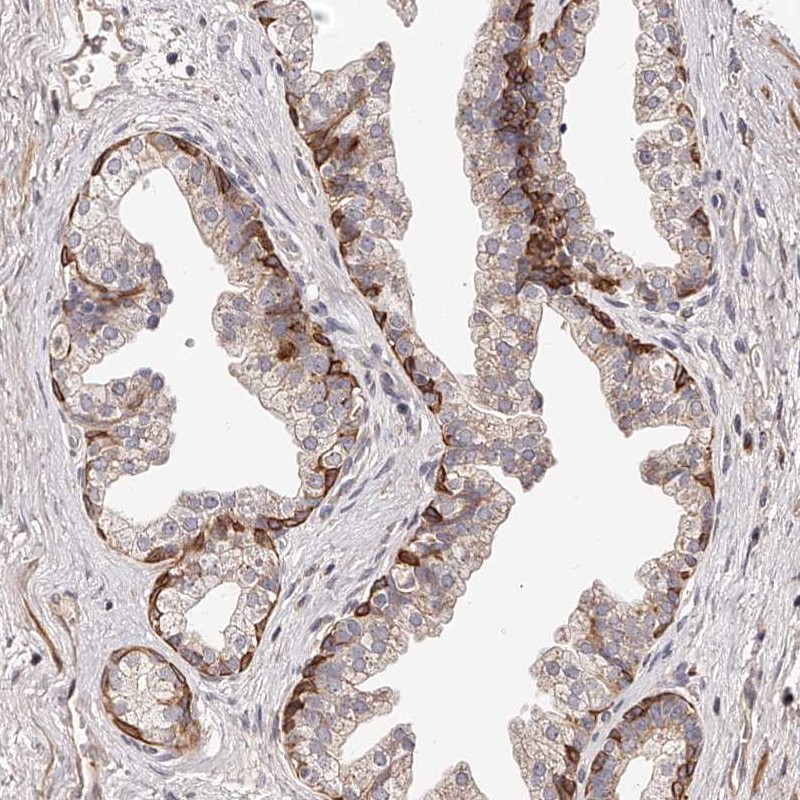

Immunohistochemical staining of human prostate shows cytoplasmic positivity in glandular cells.